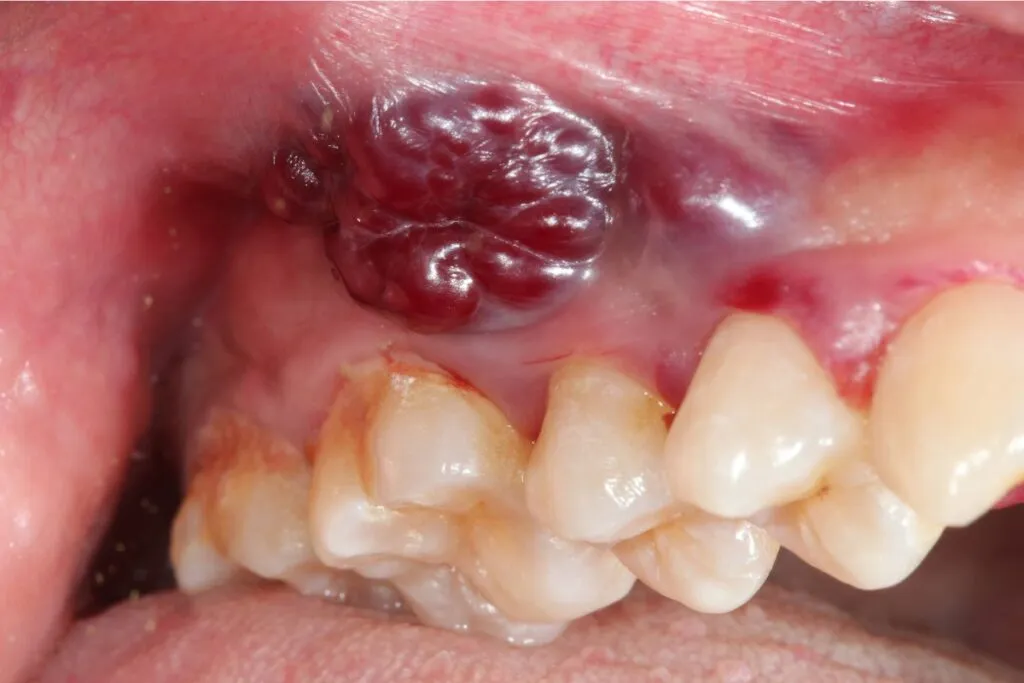

Zmiany koloru błony śluzowej: Białe i czerwone plamy, których nie wolno ignorować

Jednymi z najbardziej charakterystycznych wczesnych objawów są zmiany koloru błony śluzowej, których nie da się zetrzeć. Mówimy tu o białych lub szarych plamach, nazywanych leukoplakią, oraz o czerwonych plamach, czyli erytroplakii. Leukoplakia to zgrubienie błony śluzowej, które może być płaskie lub lekko wypukłe. Erytroplakia natomiast to wyraźnie czerwona, często aksamitna w dotyku zmiana. Chociaż obie te zmiany są stanami przedrakowymi, to właśnie erytroplakia ma znacznie wyższy potencjał zezłośliwienia i zawsze powinna być traktowana z najwyższą ostrożnością. Jeśli zauważą Państwo takie plamy, które utrzymują się dłużej niż kilka dni, konieczna jest pilna konsultacja ze specjalistą.

Stany przedrakowe: Zmiany, które wymagają natychmiastowej kontroli

Istnieją pewne zmiany w jamie ustnej, które same w sobie nie są jeszcze rakiem, ale mają znacznie zwiększone ryzyko transformacji nowotworowej. Nazywamy je stanami przedrakowymi. Do najważniejszych należą wspomniane już leukoplakia i erytroplakia, a także liszaj płaski. Każda z tych zmian wymaga natychmiastowej kontroli lekarskiej i regularnego monitorowania. Moim zdaniem, traktowanie tych stanów z należytą powagą to jeden z najważniejszych elementów wczesnej profilaktyki raka jamy ustnej.